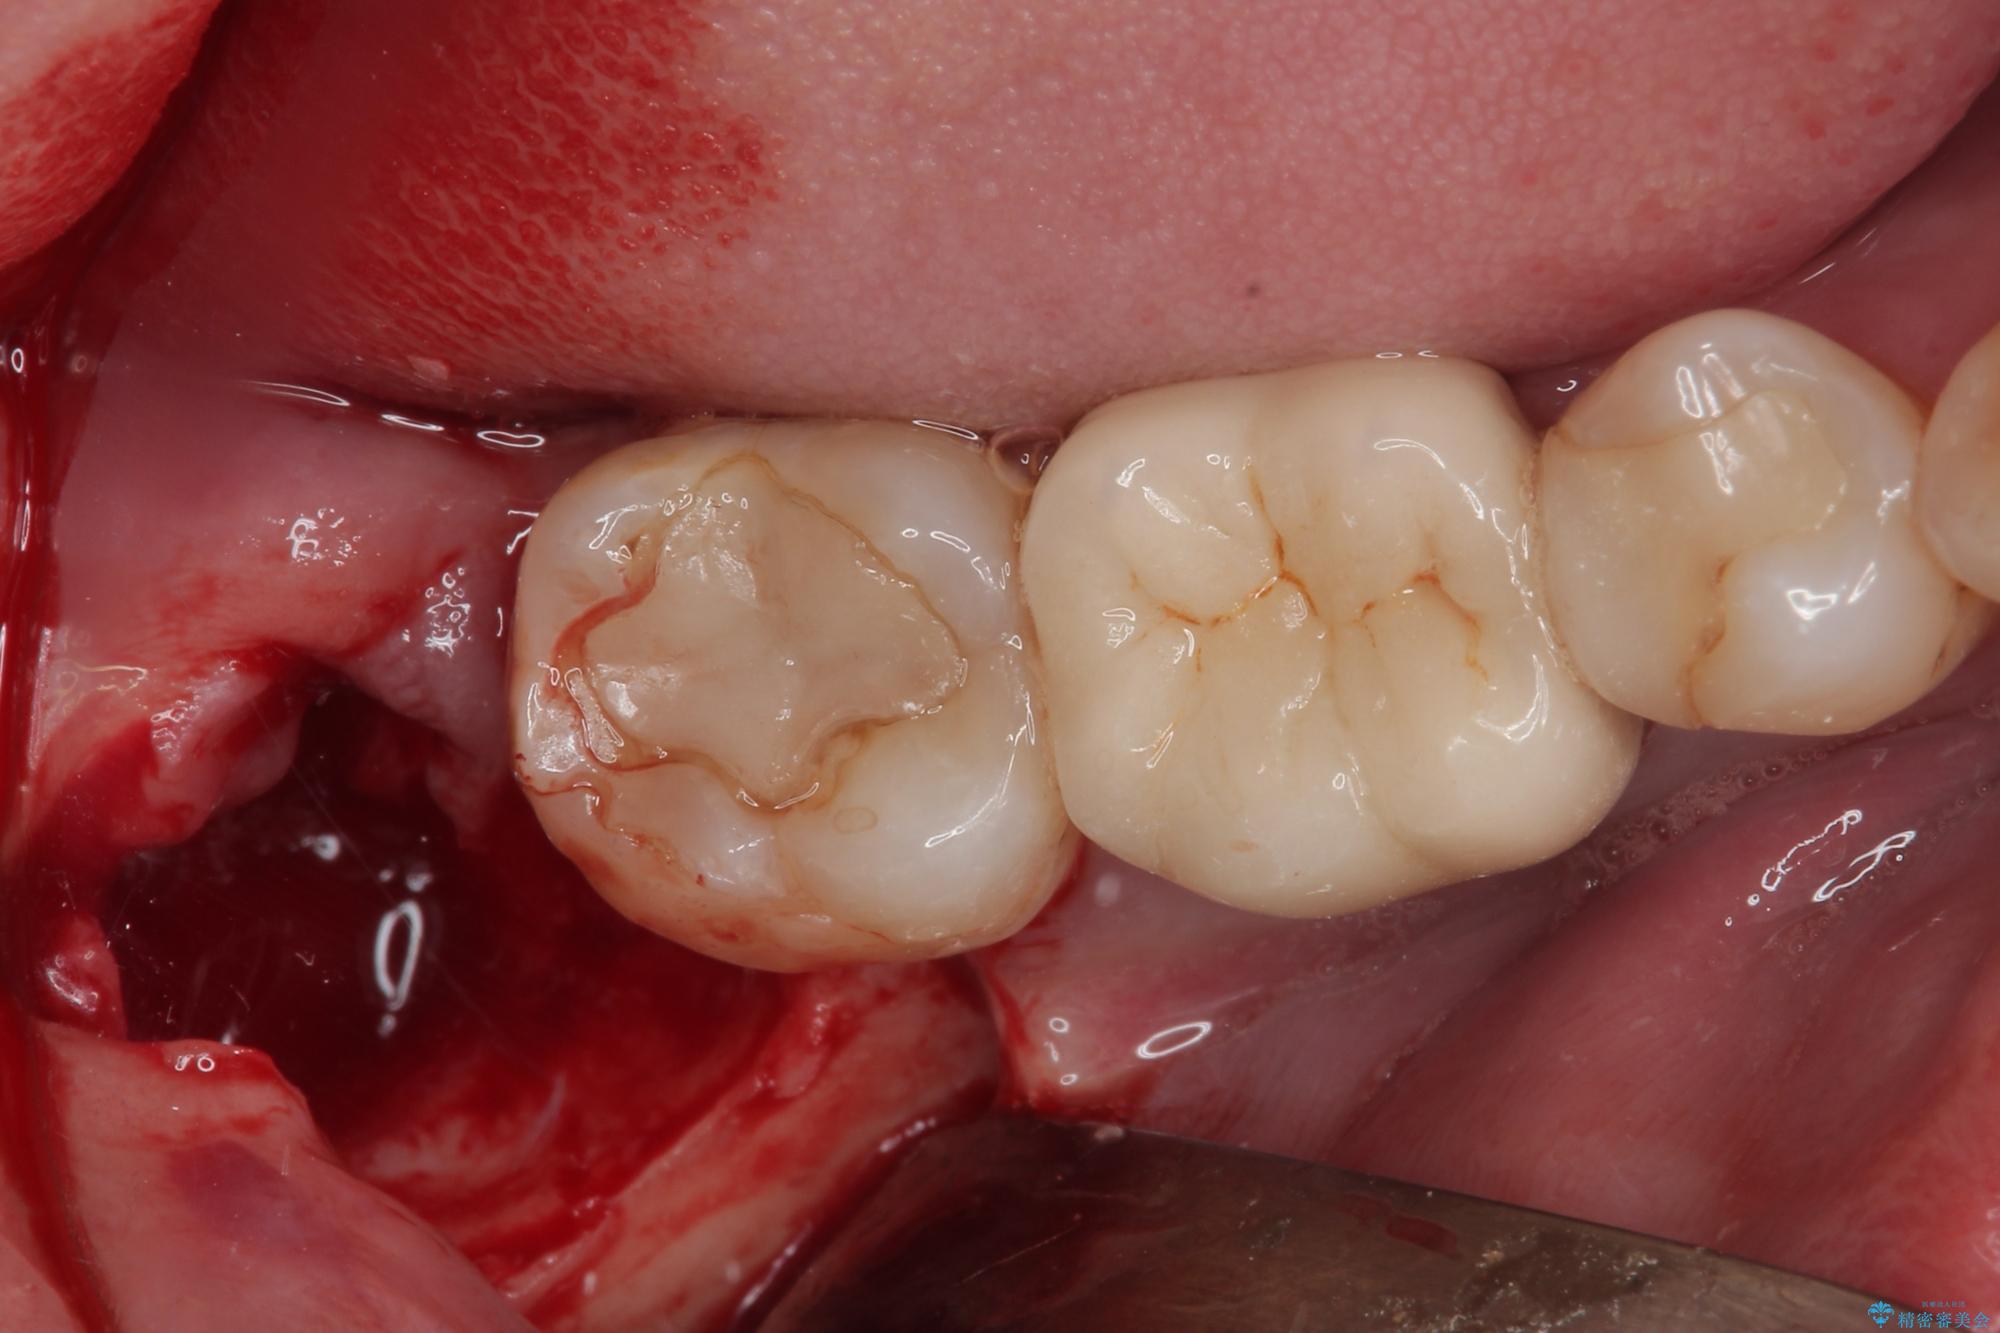

- 右下の親知らずを抜きたいとのことで来院された患者様です。

CTで神経の位置などを確認し、抜歯術を行いました。

しっかり麻酔が効いたことを確認してから安全に抜歯を行いました。